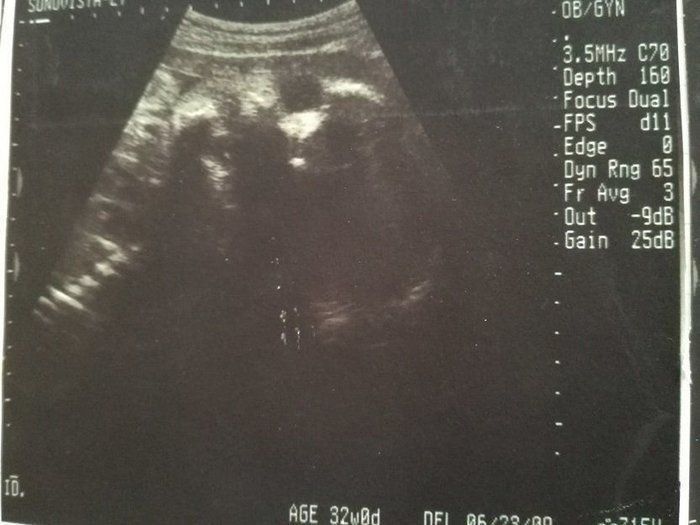

ママにエールさんの妊娠32週目のエコー写真

2度“逆子”になった胎児はもう小学生!子どもと共に読み返した当時の日記&エコー画像

推定体重1803g。「平均的だから、成長も問題ない」と先生から説明を受けました。赤ちゃんは性別をまだまだ内緒にしているよう。出産も近づきつつあるこの時期、動けるときは運動を兼ねてお散歩したり、劇場などで開かれるランチタイムコンサートなどに行ったりしました。音楽と共に胎動を感じるときは、我が子と一心同体でその瞬間を楽しんでいるような幸せな心地がしました。